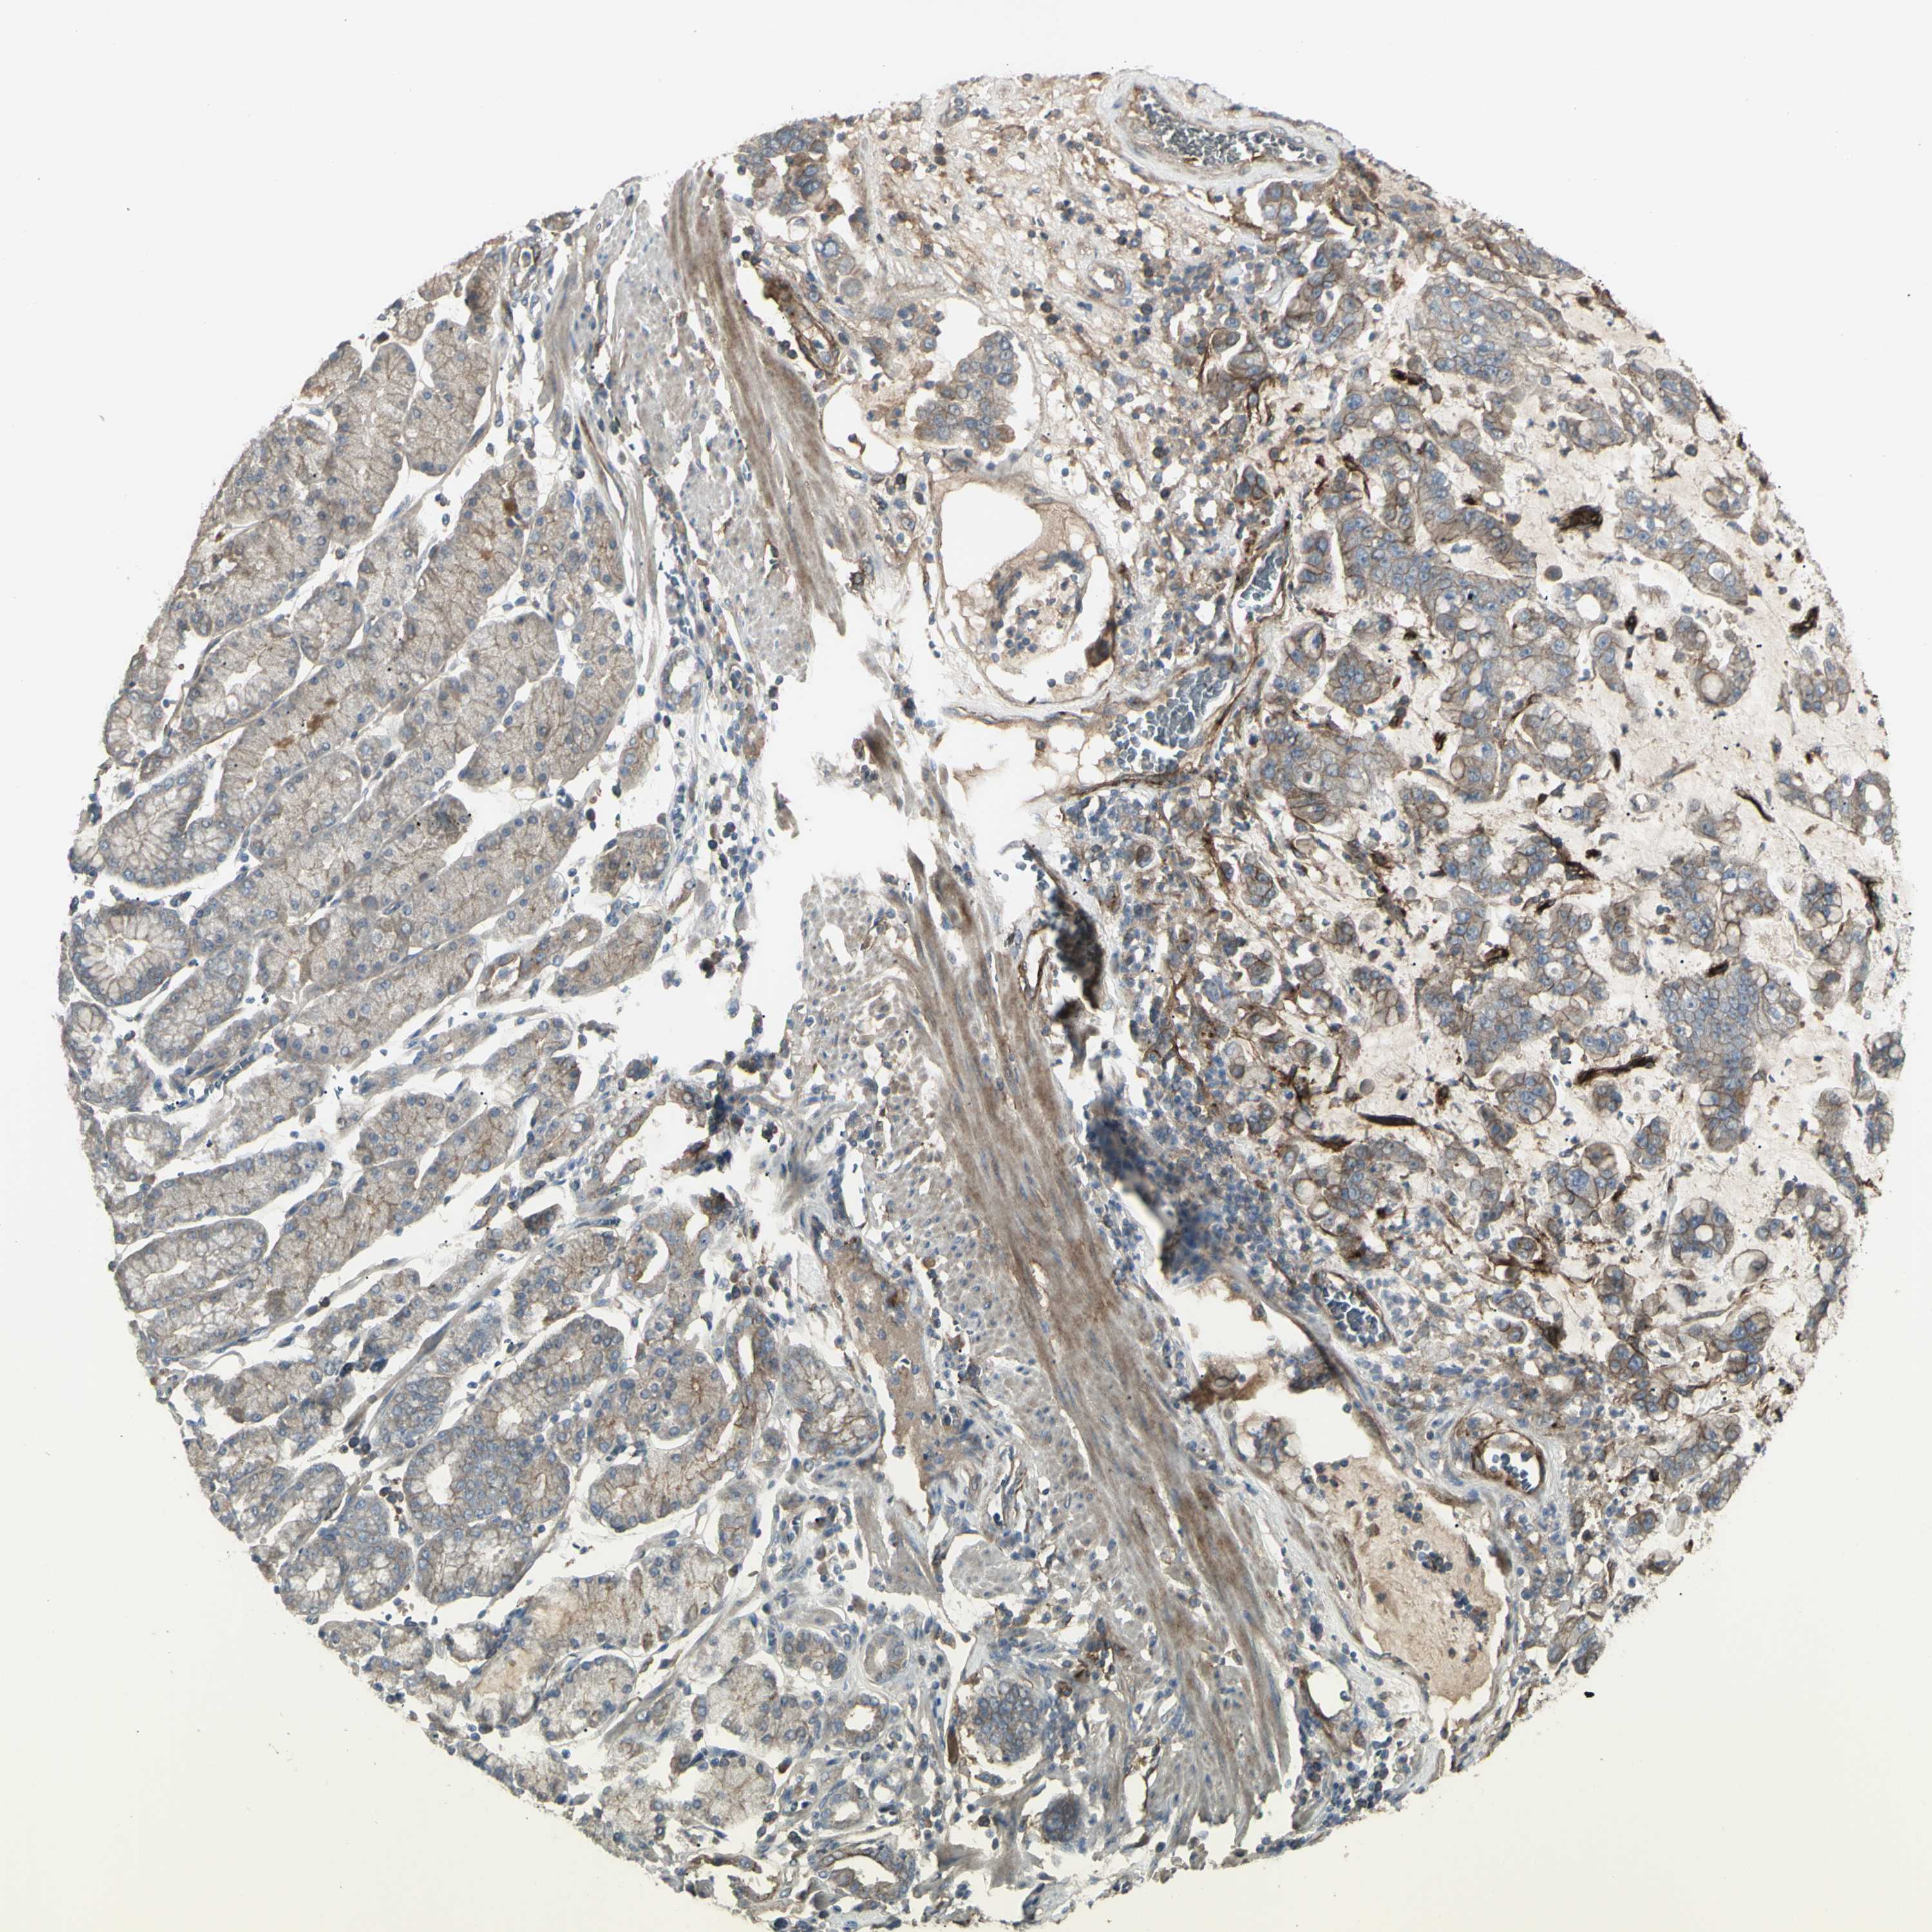

STOMACH CANCER - Protein expressioni

A mouse-over function shows sample information and annotation data. Click on an image to view it in a full screen mode. Samples can be filtered based on level of antibody staining by selecting one or several of the following categories: high, medium, low and not detected. The assay and annotation is described here.

Antibody stainingi

Antibody staining in the annotated cell types in the current human tissue is reported as not detected, low, medium, or high, based on conventional immunohistochemistry profiling in selected tissues. This score is based on the combination of the staining intensity and fraction of stained cells.

Each image is clickable and will lead to virtual microscopy that enables deeper exploration of all samples and also displays staining intensity scores, fraction scores and subcellular localization as well as patient and tissue information for each sample.

Antibody HPA009285

Antibody HPA017139

Antibody CAB017826

Staining

High

Medium

Low

Not detected

Intensity

Strong

Moderate

Weak

Negative

Quantity

>75%

75%-25%

<25%

None

Location

Nuclear

Cytoplasmic/membranous

Cytoplasmic/membranous,nuclear

Adenocarcinoma, NOS

Adenocarcinoma, High grade